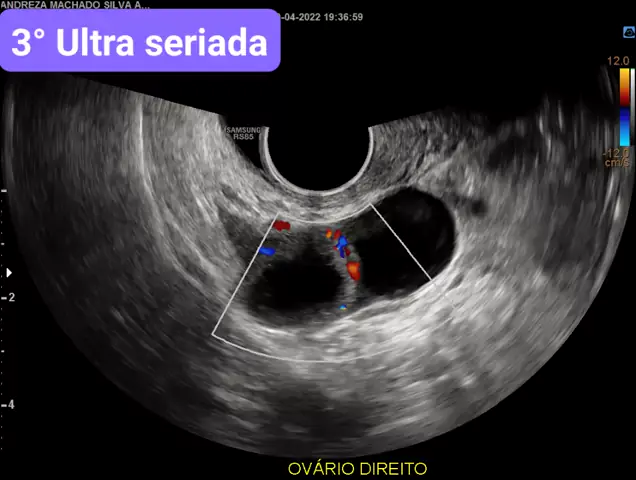

3°Ultra seriada/ para ver corpo lúteo 🎯 #ultra #vembebe #ovulação #vempositivo